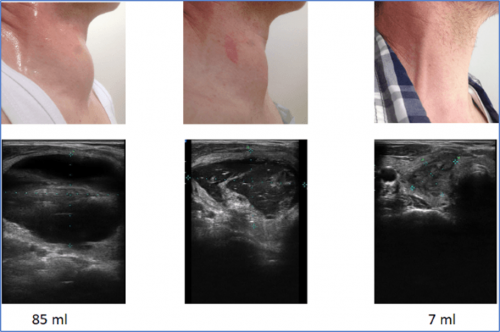

Langzeitverlauf nach einmaliger Thermoablation (Mikrowellenablation). Knoten können bis zu 2 Jahre nach Therapie weiterhin an Volumen verlieren.

Patientenfall 4- Schilddrüsenzyste

Verlauf einer rezidivierenden Schilddrüsenzyste nach einmaliger Behandlung durch Prof. Dr. Dr. H. Korkusuz. Die Zyste läuft nicht erneut voll.